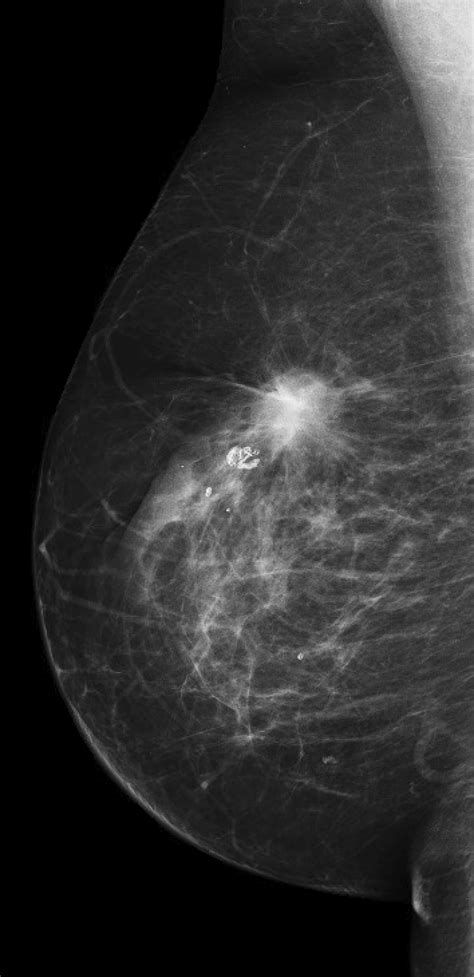

• Mammogram: An X-ray of the breast to detect any masses or abnormalities.